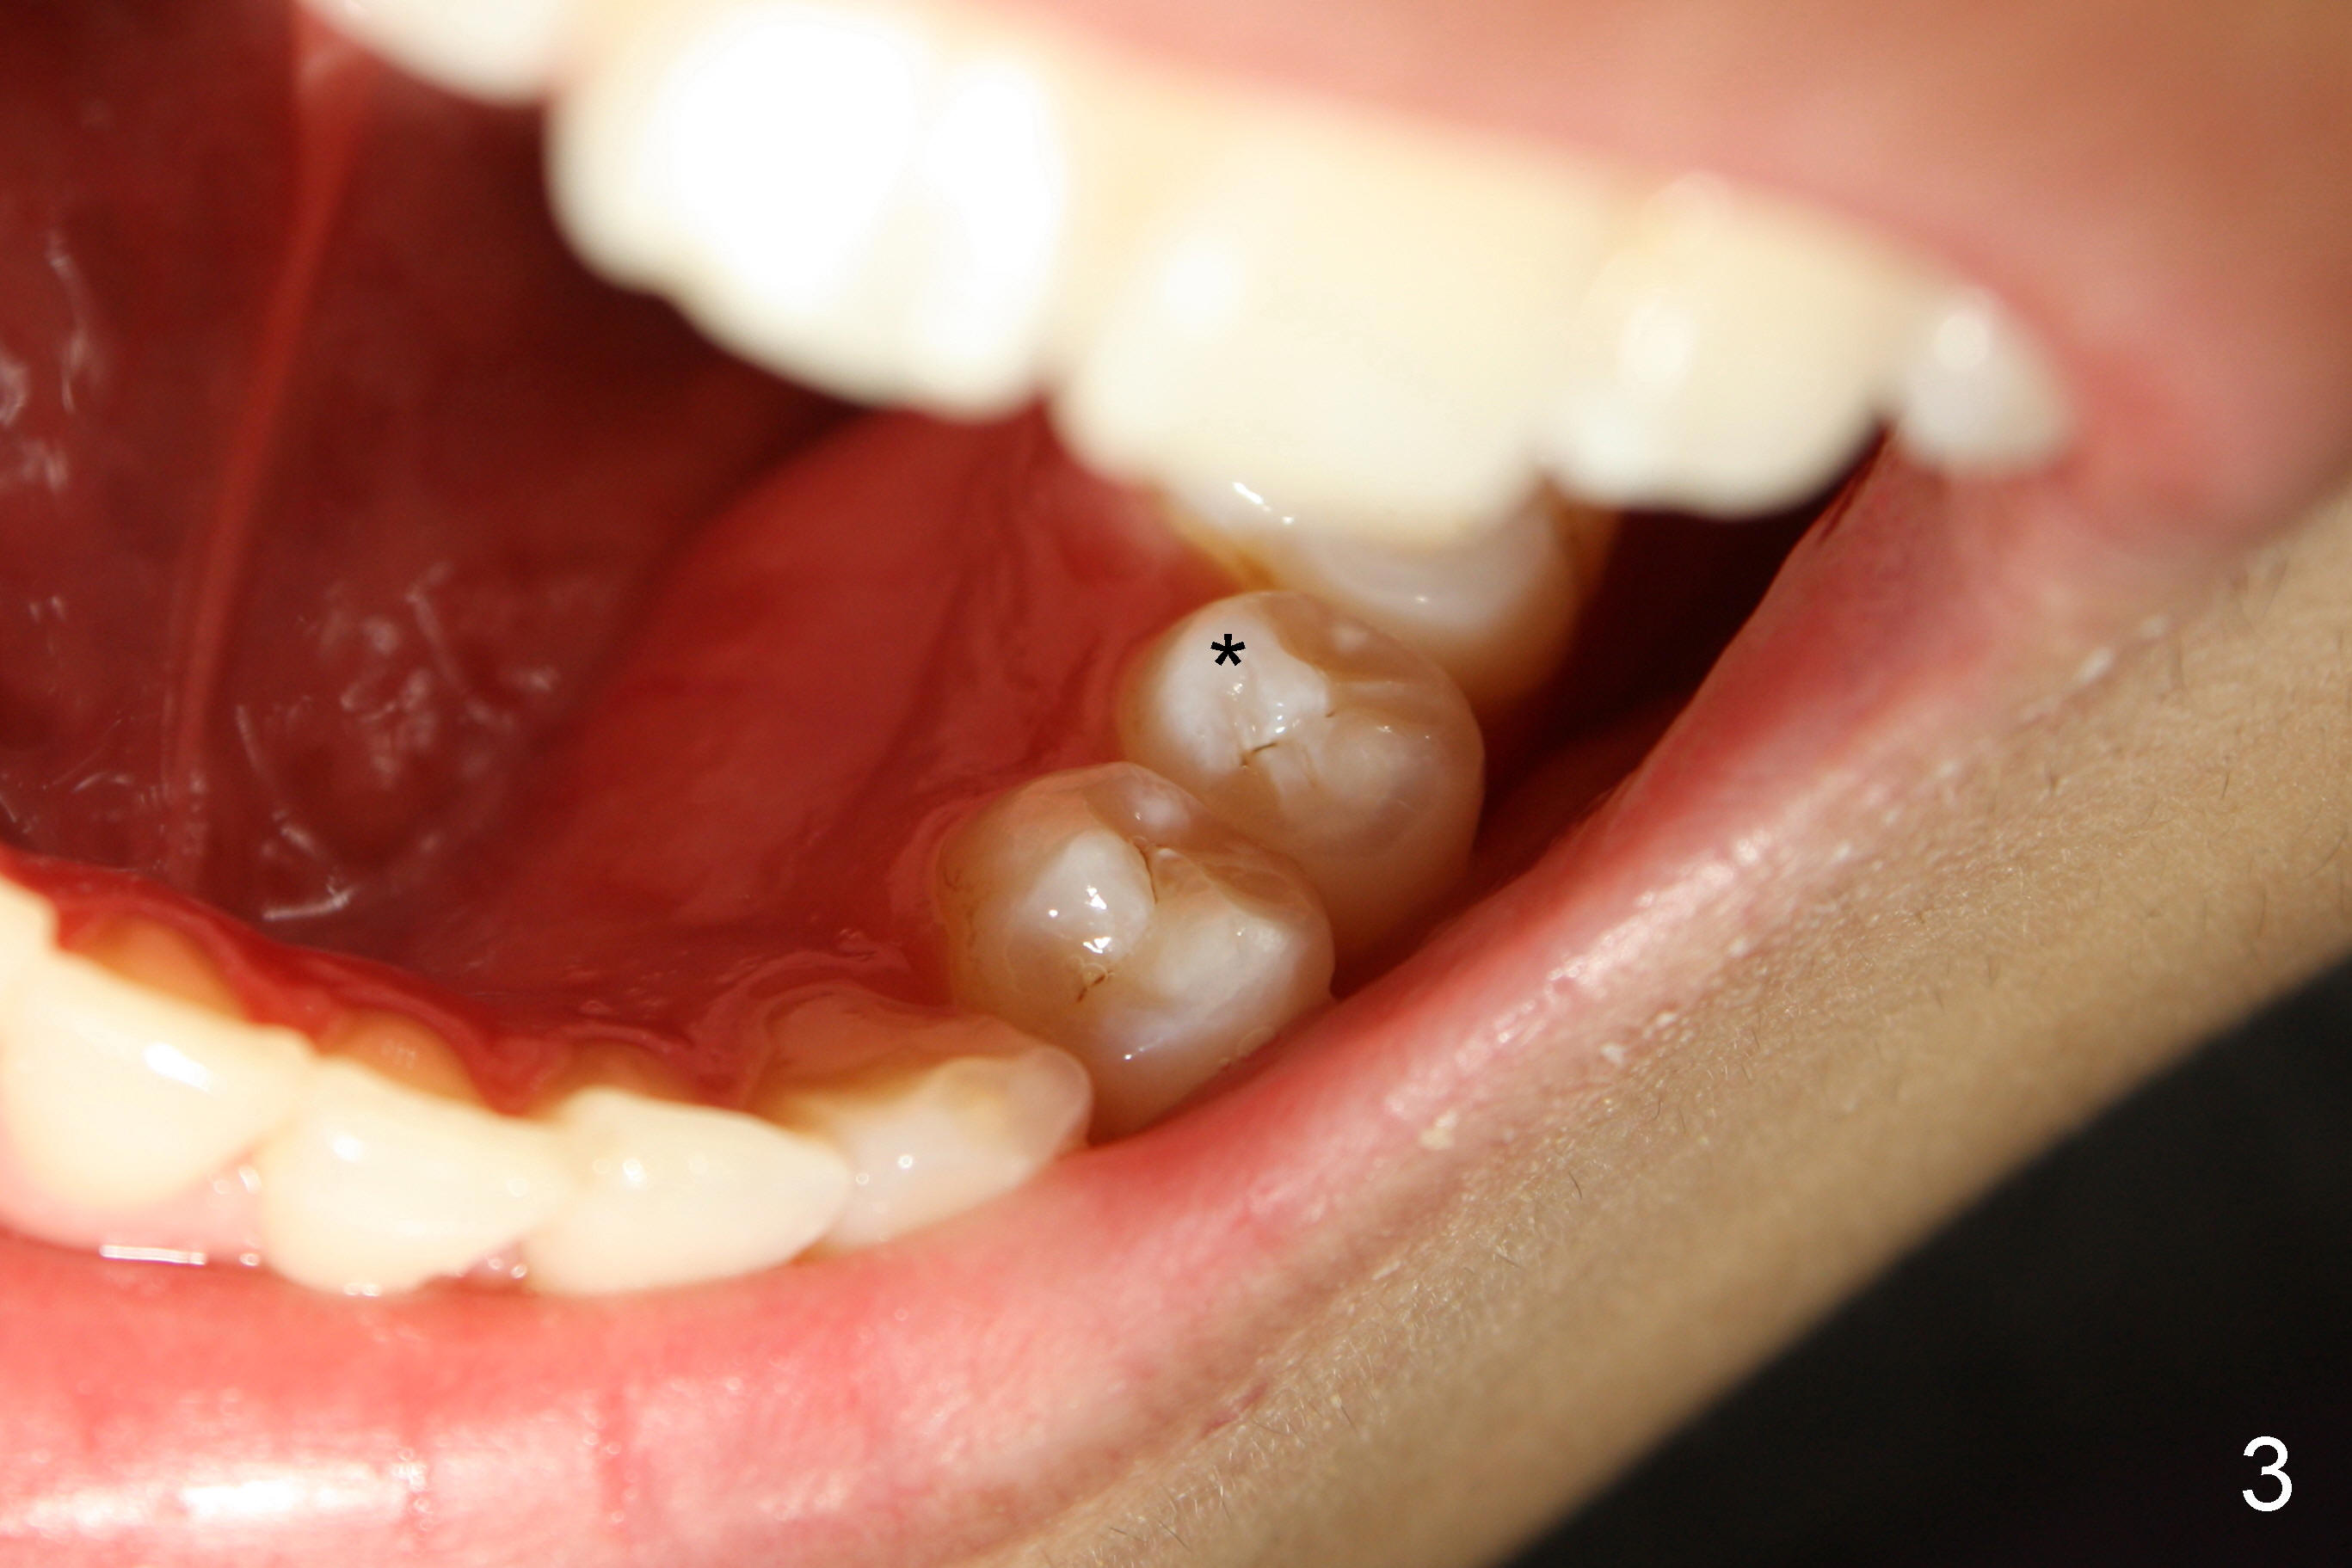

治疗前告诉病人,如果治疗后瘘道不消失,可能需要进一步治疗(根尖切除术)。根管开口(Access)如图二插图表示,唯一不理解的是这个牙齿只有一个根管,似乎偏向颊侧,扩大针尽量往舌侧拉,颊舌侧之间好像有狭部感觉(Isthmus)。Apex Locator运转正常,说明根尖关闭。预先弯曲扩大针:10-20号,然后使用40/.06 rotary file,太容易达到根尖,所以逐步使用扩大针治七十号,但是逐渐失去working length (WL),最后七十号牙胶尖插不到根尖(图四(箭头:根尖阴影)),而40/.06牙胶尖在有冲洗液下容易达到WL,接触(Binding)不够紧密,好像再大一号扩大针(四十五号)就达到不了WL。由于时间问题,使用AH26 Plus Paste,主牙胶尖40/.06,以及medium and fine medium accessory gutta percha(各一根)完成充填(图五),最后树脂充填,不准备做牙冠,观察。